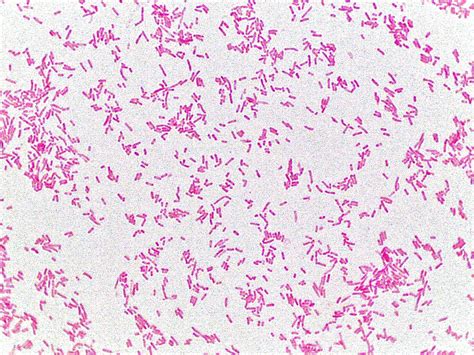

Gram-positive bacteria rods are a fascinating group of microorganisms that play significant roles in various ecosystems and human health. These bacteria are characterized by their unique cell wall structure, which retains the crystal violet stain used in the Gram staining procedure, giving them a purple color. This distinctive feature sets them apart from Gram-negative bacteria, which appear pink or red due to the counterstain safranin. Understanding Gram-positive bacteria rods is crucial for microbiologists, healthcare professionals, and researchers alike, as they are involved in both beneficial and pathogenic processes.

• Shape: As the name suggests, Gram-positive bacteria rods are rod-shaped, or bacilli. This shape can vary slightly, but it is generally elongated and cylindrical.

• Staining Properties: Due to their thick peptidoglycan layer, Gram-positive bacteria retain the crystal violet stain during the Gram staining process, appearing purple under a microscope.

• Gram Staining: This is the initial step in identifying Gram-positive bacteria rods. The sample is stained with crystal violet and iodine, followed by a counterstain with safranin. Gram-positive bacteria appear purple under the microscope.